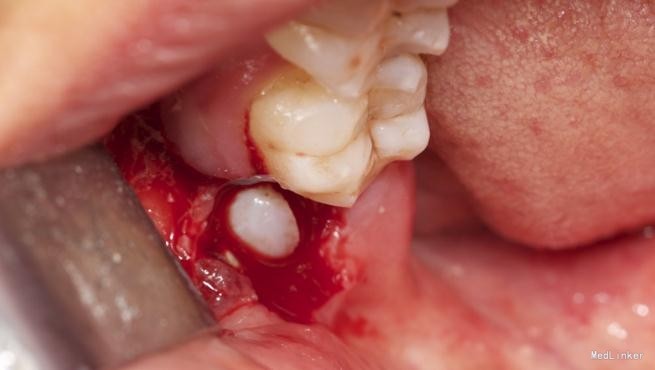

拔除术

挺好的病例,图片也很清晰,牙齿分的很好,我之前拔过类似的牙,牙齿分开后近中撬不动,最后又T型分开近中后才弄出来

水平阻生拔除的难度还是很大的,图片看着创伤不是很大,能不能把您拔牙时的阻力分析和该牙具体的拔牙步骤给我们说一下呢?谢谢~